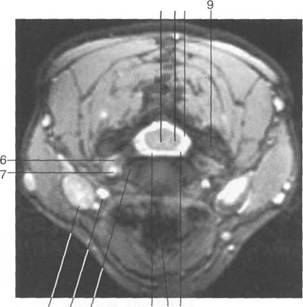

К моменту рождения (рис. 3.1) тело позвонка почти полностью состоит из к 141s183b 86;стной ткани, за исключением лимбусов, которые остаются хрящевыми. Дуга представлена двумя половинами, не слившимися ни с телом позвонка, ни между собой. Суставные отростки сохраняют перифе

Ti

(lamina)

(uncus)